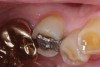

Fig. 4 Defective margins. Mandibular first molar with an amalgam restoration with defective margins.

Figure 4  Defective margins. Mandibular first molar with an amalgam restoration with defective margins.

Figure 4